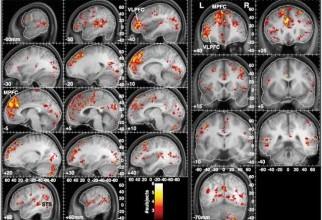

Orientările politice sunt vizibile în activitatea cerebrală